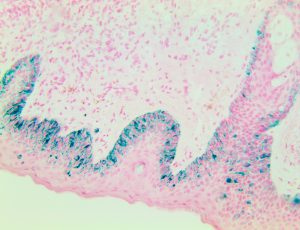

Bio SB has developed high affinity IVD monoclonal antibodies for fast immunohistochemistry (IHC) detection of melanoma, basal cell carcinoma (BCC), squamous cell carcinoma (SCC) and other Mohs surgery related conditions. Combined with our innovative IHC detection systems, we are opening the doors to a faster and more accurate immunohistochemistry applicable to Mohs surgery.

Bio SB has developed a fast, non-biotin monovalent Fab micropolymer IHC detection system for the detection of IVD antibodies for melanoma, BCC, SCC and other Mohs surgery related conditions. Our innovative IHC detection systems have opened the doors for a faster and accurate immunohistochemistry applicable to Mohs surgery.